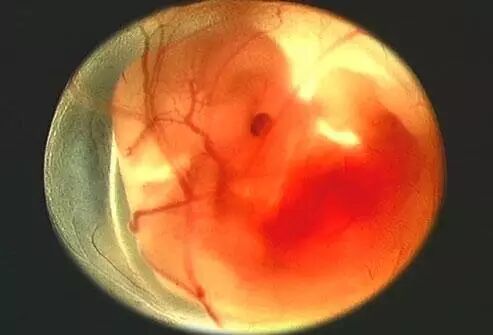

准确地说,现在的我还只是一个胚芽。我在你的身体里飞快地长,成功地长出了三胚层。三胚层将来会长成我身体的不同部分,作为“成长核心”。

小精子说:”我怕怕——妈妈要保护我哦!要是这个时候出点事情,那我可从“根”上出问题了。你可不能让我输在“起跑线”上啊!

第二个月:打实基础

妈妈,到现在为止,你的宝贝已经进你身体里这件事情还是我们俩之间的秘密,别人一点儿也看不出。(当然宝贝有些儿担心,直觉告诉我,你已经把这个秘密告诉了爸爸。)这段时间我可忙了。

宝贝在自己的房子里拼命地生长:我的心脏开始有规律的跳动,并且开始供血。我的心跳达到150次/分钟,相当于大人们心跳的两倍,心脏也化分为左心房和右心室。

连接脑和脊髓的神经管开始工作;我的四肢、五官等都已经开始有了雏形。

小胎儿的话:“我怕怕,妈妈情绪波动过大,导致胎儿颚裂或唇裂。乱吃药会导致胎儿先天畸形。